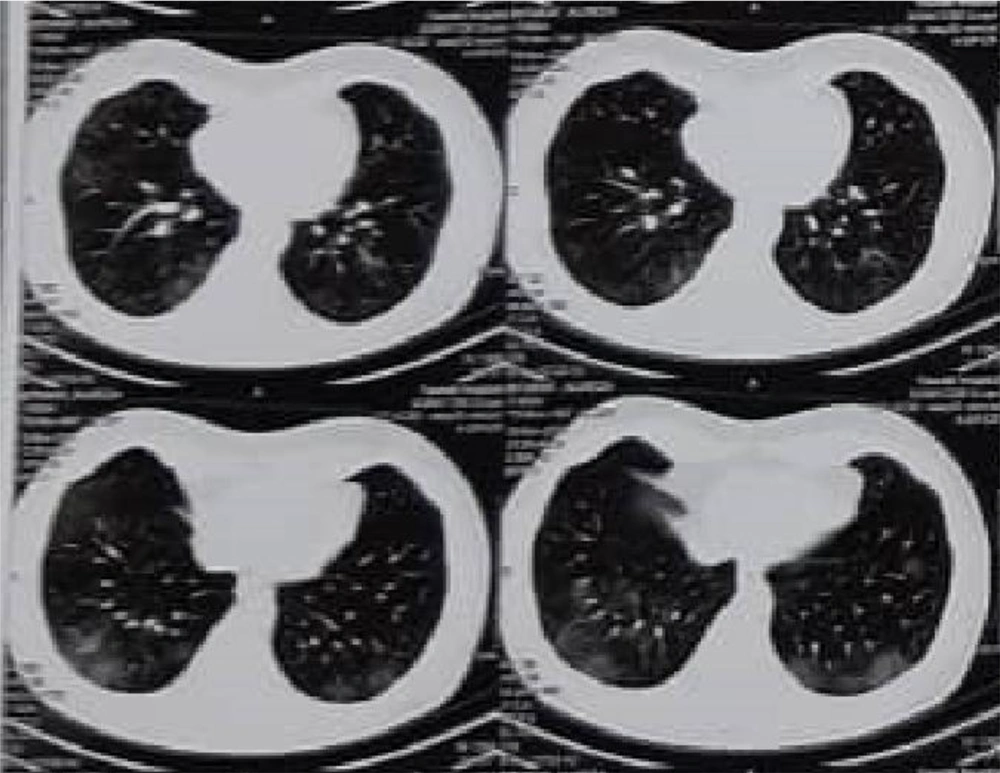

An 18-year-old boy with a history of kidney transplantation for five years due to a neurogenic bladder was admitted to our pediatric nephrology clinic. He had a fever, cough, mild diarrhea, and severe anorexia for two weeks. At the time of admission, he had respiratory distress. SPO2 was 82% on room air, which increased to 95% with supplemental oxygen using a face mask. Physical examination showed tenderness at the transplanted kidney site, conjunctivitis in both eyes, mild dehydration, and crackles in the right lower lung. Urine output decreased to 0.4cc/kg/hour. In primary lab tests, WBC was 2.5 × 103/mm3, with 30% lymphocyte, HB 9 mg/dL, platelets 140 × 103/mm3, Cr 5 mg/dL, and (pre-infection serum creatinine was 2.5 mg/dL). Nasopharyngeal PCR was positive for SARS-CoV2. At the time of admission, while Chest X-Ray (CXR) had no specific findings in the patient, the chest computed tomography (CT) scan (Figure 1) showed the pattern of COVID-19 pneumonia in the form of ground-glass opacities in both lungs. He was admitted to our nephrology ward. Initially, ceftriaxone was initiated for the patient. However, on the third day, due to deterioration of the patient's respiratory status and general condition, he was transferred to the intensive care unit (ICU) for cardiopulmonary monitoring and hemodialysis, and broad-spectrum antibiotics were prescribed and continued throughout the patient's hospitalization despite all the negative cultures in terms of the virus, bacteria, and fungi. Lopinavir-ritonavir was then initiated. MMF and cyclosporine were stopped, and corticosteroid increased and changed to a stress dosage. Since acute febrile illness causes minor stress, 30 - 50 mg/m2/day of hydrocortisone (this amount increased 3 - 5 times in case prednisolone was used) was given to the patient until the fever stopped, and then, the drug was tapered and returned to the patient's previous consumption (14). The respiratory condition was improved after one week, and the patient was transferred to the ward. However, the graft was lost and he underwent dialysis.